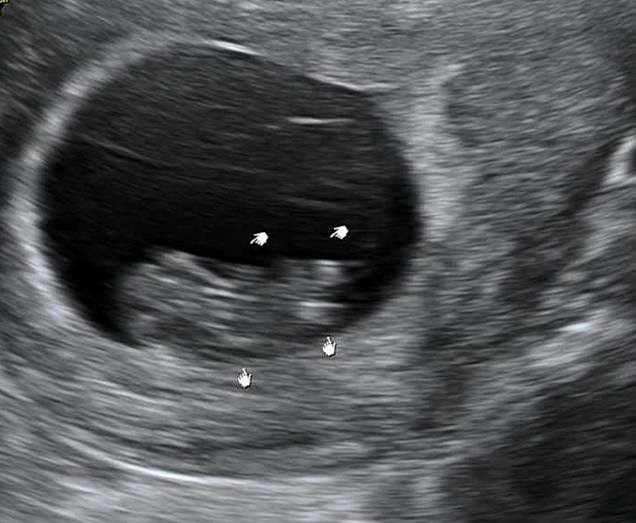

[태아-임신 10주 태아크기 초음파 모습]

-임신 10주 태아 초음파

초음파를 통해 보여진 태아는 머리와 몸통, 팔다리가 분명하게 구분되어 있고, 양수 속에서 팔다리를 움직이고 있다. 임신 10주가 되면 태아는 팔목을 구부렸다 펼 수 있게 되고, 발의 모든 기관을 갖추게 된다.

태아의 심박수는 보통 150bpm~ 18-bpm 이며 초음파를 통해 확인한 심박수는178bpm으로 성인의 심박수보다는 두 배정도 빠르다. 초음파를 통해 탯줄을 육안으로 확인할 수 있었고, 태아는 이 탯줄로 태반에 연결되어 양분을 흡수한다.